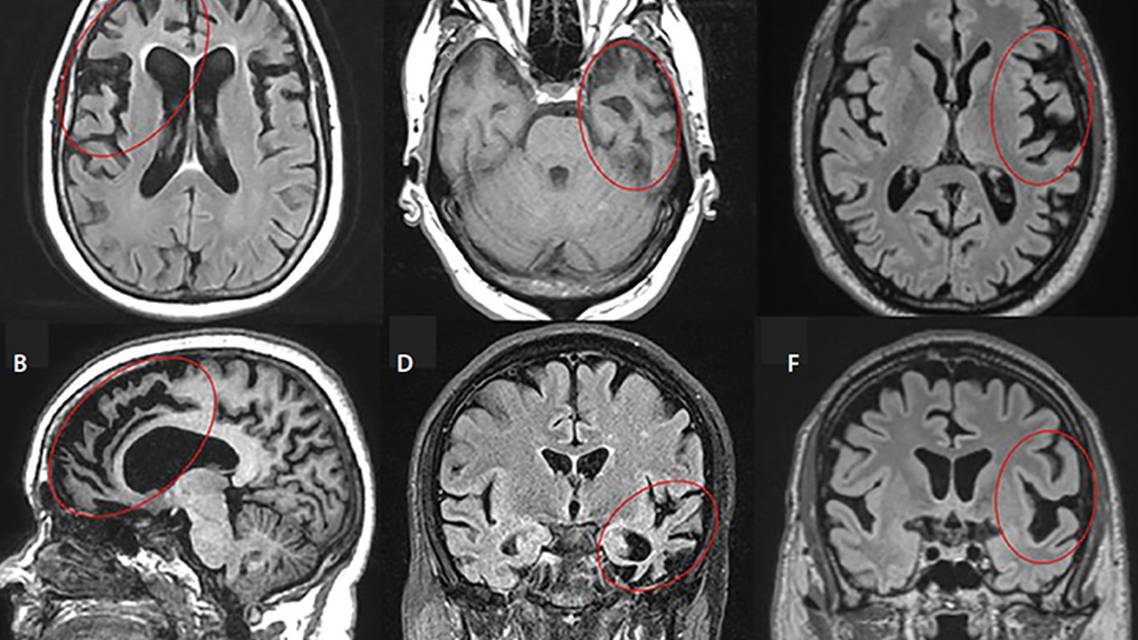

Characteristic patterns of atrophy involve the right frontal or right temporal lobes, although atrophy may be difficult to detect early in the disease course, and can overlap with normal controls.13 Bilateral frontal lobe involvement, when present, is associated with nonfluent aphasia (Figure). Genetic FTD is associated with characteristic patterns of atrophy. With C9ORF72 expanded repeats, atrophy in the frontal lobes predominates, and milder atrophy is seen in the anterior temporal, parietal, and occipital lobes, cerebellum and thalamus. With MAPT mutations, anteromedial temporal atrophy predominates. With GRN mutations, there is asymmetric temporal, insular, and parietal lobe atrophy.14,15 Although white matter is typically bland on T2-weighted MRI, imaging in late stage FTD and patients with GRN mutations may show extensive white matter hyperintensities.16 On fluorodeoxyglucose-positron emission tomography (FDG-PET) and single photon emission tomography (SPECT), bvFTD demonstrates hypometabolism or hypoperfusion in the bilateral frontal lobes, or the right temporal lobe, distinguishing it from AD with diagnostic accuracy of 80% for SPECT and 90% for FDG-PET (Figure).17-19

Characteristic asymmetric atrophy of the dominant anterior temporal pole is observed in svPPA (Figure).25 Over time, the contralateral temporal lobe is also affected.

Asymmetric atrophy affecting the dominant inferior frontal lobe is the hallmark finding in PPA (Figure).28